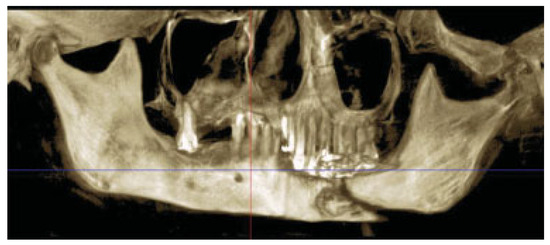

Debridement of the fibrous callous and a minimal amount of bone was removed. The soft-tissue scars were released and the bony segments were placed near their normal position and the prefabricated 2.5-mm locking reconstruction plate was applied (Figure 9). The dissection was subperiosteal due to the need to debride the bone. While Luhr’s principle of supraperiosteal dissection and its use in atrophic mandible fractures was discussed prior to surgery, it was felt that it would be difficult to achieve it with devitalized bone fragments present and the need to immediately graft the area due to the continuity defect. The bony defect was replaced with an alloplastic material and a mixture of BMP and β-tricalcium phosphate. The tissue was undermined to allow for soft-tissue coverage over the plate. Postoperative images show good restoration of the segments (Figure 10a,b). The total time of the procedure was 2 h and 26 min.

Figure 10. (a) Frontal radiograph showing alignment of the mandible. (b) Panoramic radiograph with plate in place and alloplastic material present.